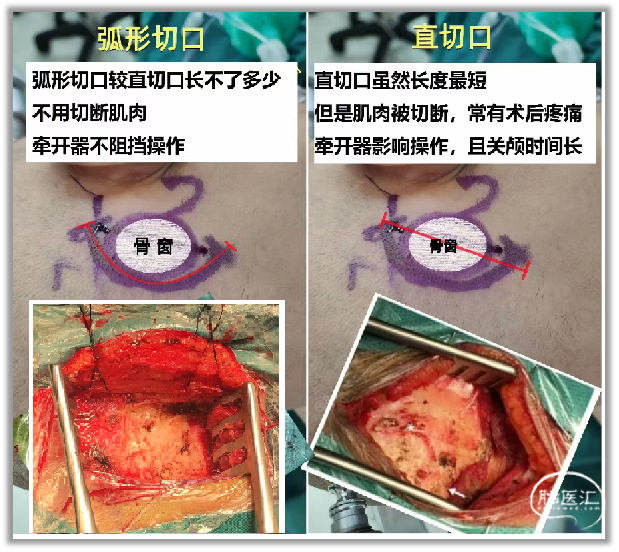

▼9.根据术前测量的“耳根后缘”与“乙状窦后缘”的距离。沿“乙状窦后缘”和横窦下1cm的位置钻孔一枚。

颅底薄层CT可观察乳突导静脉(下图)、髁导静脉发育情况。还可了解乳突气房的发育情况,对于防止术后脑脊液漏非常重要。